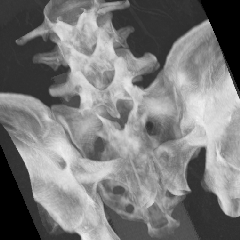

MPR表示について

CTやMRIなどの医療機器によって生成されたスライスシリーズ画像を表示する場合、MPR(多断面再構成)表示法は、非常に有効な読影方法であり、特に任意角度の斜断面画像の再構成(Oblique)表示法は、臨床診断に非常に有用かつ重要な読影手法となっています。

ImageClarityのMPR表示機能は、エンジンレベルで実現したもので、任意空間原点と任意3D方向の断面を表示することが可能になっており、補正表示をしながら実用レベルの高速表示を実現し、3D処理開発キットとしても非常に利用しやすいAPIを提供しています。 MPR以外に、任意サイズのMIP(最大値投影)表示法もサポートしています。

MPR/MIP表示